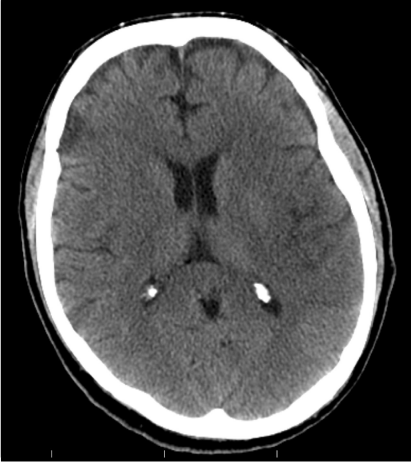

Vital signs on presentation at the outside hospital were: Temperature 38.1 F, Heart Rate of 90-101 beats/minute, Respiratory Rate 20-40 breaths/ minute, mean arterial pressure of 70 mmHg and oxygen saturation of 94% on VentiMask 40%. On examination at our hospital he was found to be tachypneic at 33 breaths/minute requiring Bi-level positive airway pressure (BiPAP), heart rate-106 beats/minute, mean arterial pressure-64 mmHg and oxygen saturation of 90% on VentiMask 40%. He appeared confused and lethargic. Neck exam was positive for jugular venous distension. He had decreased breath sounds bilaterally and the LVAD hum was heard on cardiac exam. On neurologic exam, he did not follow any commands, was aphasic with a right facial droop and had right hemiplegia. On checking with the outside hospital, due to his acute distress and lethargy, a neurologic exam was not performed. Laboratory tests on admission were consistent with hemolysis and acute renal failure (Table 2). LDH was elevated at 3012 (IU/L) up from<500 a week ago. Chest radiography was consistent with pulmonary edema (Figure 1). CT Head revealed a left non-hemorrhagic MCA infarct with mild mass effect and mild midline shift from left to right (Figure 2). Urine in his Foley bag was orange- red in color. A stat echocardiogram (Figure 3) obtained revealed a dilated left and right ventricle and an aortic valve opening every beat that was opening every other beat on his last clinic visit, 3 weeks ago. This further confirmed the working diagnosis of an acute LVAD thrombus complicated by an embolic event leading to the acute ischemic infarct. An emergent Neurology consultation was obtained and after reviewing his physical exam and CT-brain with the Neurology team, the diagnosis of acute ischemic stroke with significant right hemiplegia was confirmed. Since he was outside the recommended treatment window for thrombolytic administration for his acute stroke (9hours against the recommended, the Neurology team recommended against the use of systemic thrombolysis due to the increased risk for bleeding vs. reducing infarct size.

Figure 2 CT- Head at Presentation. Large left non- hemorrhagic middle cerebral artery infarct with mild mass effect.